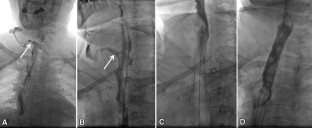

Fig. 2